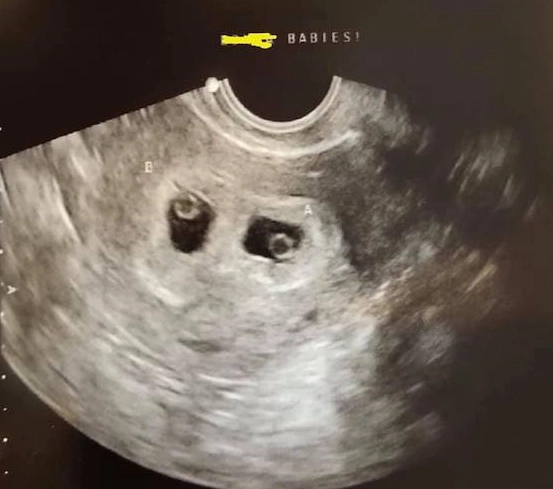

What does a healthy 5-week ultrasound look like?

If you have an early scan, manage your expectations. You're not going to see a recognizable baby or hear a heartbeat. A healthy 5-week ultrasound primarily shows a gestational sac snugly located inside the uterus. By the end of the week, we hope to see the yolk sac. The main goal here is to confirm the pregnancy is in the right place. Seeing a fetal pole or heartbeat is a bonus but not the standard at this exact point.